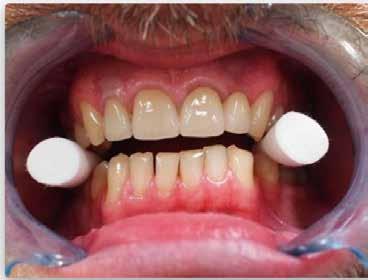

A 28 éves hölgypáciens is elsősorban a szép mosoly elérésének igénye miatt szeretett volna fogszabályozást, bár tudomása volt a mélyharapásáról (1–5. képek).

A kezelési célokat a fogívek tágítása a megfelelő mosolyszélességhez és az alsó frontfogak torlódásának feloldásához, valamint a mélyharapás és a kismértékű disztálharapás korrekciója jelentették (6–11. képek).

Passzív önligírozó fix fogszabá-

lyozó készülékkel 15 hónapig tartott a kezelése. Az ilyen mélyharapásos esetekben nagyon fontos, hogy a harapásemelésnél nem történik intrúzió a felső fogíven, mert az kifejezetten negatívan befolyásolná a vertikális mosoly-display-t! A fogszabályozó kezelés után, ahogy az általában lenni szokott, a bölcsességfogak eltávolításra kerültek. Mint minden esetben, a fogszabályozás aktív fázisa után a retenció, a passzív helyben tartó fázis a kezelési eredmény megtartásához rendkívül fontos!